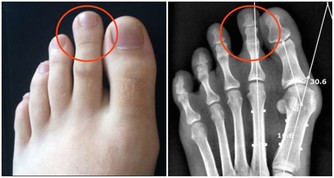

3、手掌心泛白 與常人的手掌顏色大不相同, 普通人的手掌顏色紅潤, 而患有肝病的病人手掌心泛白無血色。 4、蜘蛛痣 中間有一紅點,周圍有血絲狀, 類似於蚊蟲叮咬後的癥狀, 當用細棒一端壓迫痣中心時、全痣消失, 放開後又會出現, 這一肝病患者早期癥狀可與其他血管痣相鑑別。 據介紹,男性體表有蜘蛛痣者, 85%的人可有不同程度的肝臟組織病變, 其中約30%為肝硬化。 5、全身表現 身體乏力、容易疲勞是最常見的全身表現。 部分肝病患者可伴有不同程度黃疸, 表現為尿黃、眼睛黃和皮膚黃, 是最具有特異性的肝病癥狀(小兒生理性黃疸除外)。 黃疸過高時出現皮膚瘙癢。